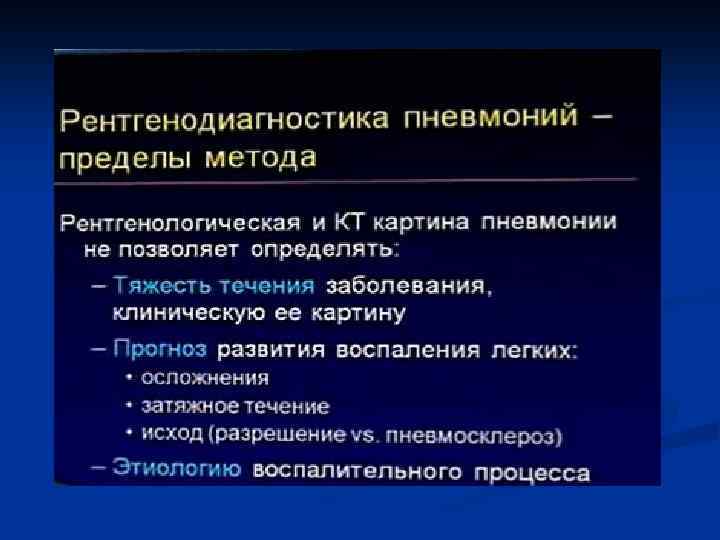

На I этапе обследования рентгенолог должен ответить на вопросы: Есть пневмония или нет 2. Локализация 3. Протяженность (если вся доля, то течение м. б. затяжное) 4. Характер пневмонии (долевой, ацинарный) 5. Первичная или вторичная На II этапе проследить изменения в динамике: 1. Рассасывание 2. Осложнения (нагноения, коллапсы) На III этапе (клинически выздоровление): 1. Полное ли рассасывание 2. Есть ли постпневмонические изменения легких (сетчатость, ячеистость) 1.

Показания к КТ грудной клетки n n n Недостаточная диагностическая информация стандартного рентгенологического исследования с наличием клиниколабораторных данных при подозрении на пневмонию Стертые клинические и лабораторные данные у больных с подозрением на пневмонию Затянувшийся кашель, субфебрилитет у больных с ОРВЗ Обострения хронических заболеваний бронхо-легочной системы Осложнения в процессе лечения больных пневмонией Затянувшиеся пневмонии

ИТАК, n Долевые и очаговые инфильтративные изменения обычно характерны для бактериальных пневмоний n Сетчатые интерстициальные изменения или сочетание инфильтративных и интерстициальных изменений типичны для пневмоний вирусной, микоплазменной, хламидийной и пневмоцистной природы, а милиарные поражения — для туберкулеза легких, генерализованного сальмонеллеза, грибковых поражений. n Инфильтративные или интерстициальные изменения в сочетании с лимфоаденопатией типичны для туберкулеза легких и пневмоний, вызванных грибами, микоплазмой, хламидиями, вирусами кори и ветряной оспы.